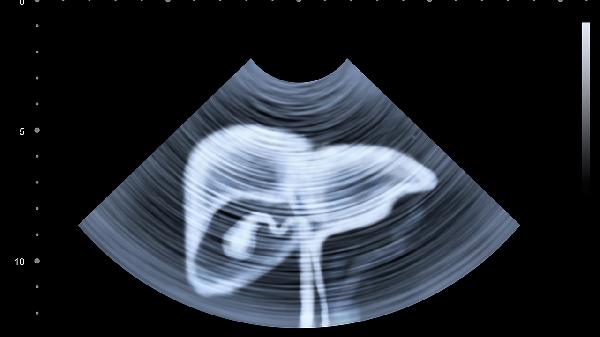

女性盆腔巨大囊肿向上推移可表现为上腹膨隆,超声检查可明确囊肿性质。生理性囊肿多可自行消退,病理性囊肿需根据性质选择药物或手术治疗。突发剧烈腹痛需警惕囊肿扭转或破裂。

建议出现持续上腹硬胀症状者记录饮食与症状变化,避免过度按压腹部。日常保持规律作息与适度运动,控制高脂高盐饮食。若伴随发热、呕血、体重骤降等危险信号,或症状持续超过两周未缓解,应及时至消化内科或普外科就诊,完善超声、CT等影像学检查明确病因。妊娠期女性出现该症状需优先排查产科相关疾病。